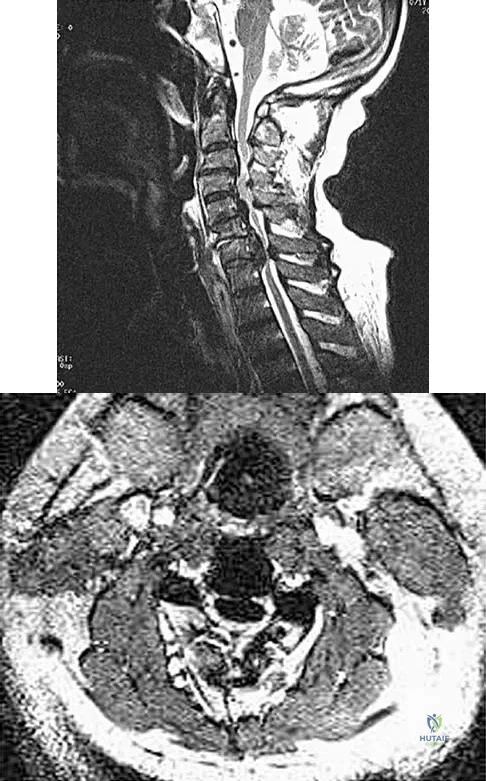

An Asian 45-year-old man has bilateral upper extremity dysfunction. Figure 35a shows a T2-weighted sagittal MRI scan of the cervical spine, and Figure 35b shows a T2-weighted axial MRI scan at the level of the C3 vertebral body. What is the most likely pathologic process?